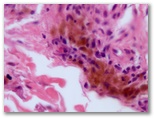

Paciente en tratamiento con amiodarona que consulta por un cuadro intolerancia luminica facial

Diagnostico